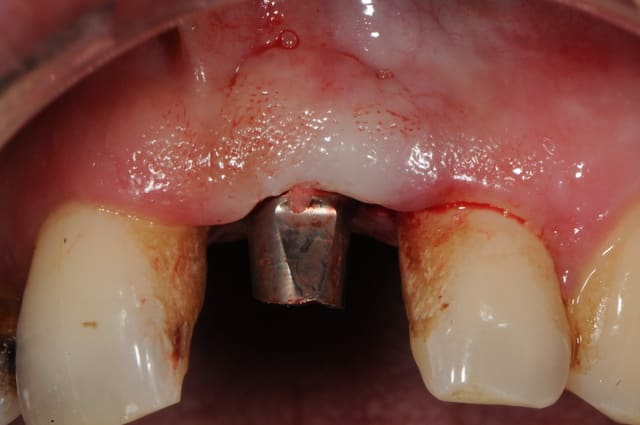

Un pilier de cicatrisation customisé ou personnalisé c'est une vis de ciatrisation individualisée : elle peut être faite de plusieurs facons par exemple à partir de ton porte implant que tu modifies par apport successif de composite.

Ca ressemble à cela :

sinon, tu peux toujours partir d'un pilier standard et tu fait une provisoire dessus qui s'adapte au mieux...

comme olivier tu en sacrifies une vingtaine, mais bon, c'est pas grave tu peux t'en re-servir.